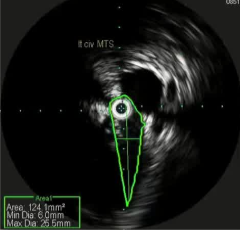

![]() if you look hard enough,如果你的眼睛睁的足够大,你就不难发现,通常下肢血栓清除后是潜在的静脉狭窄 术前的影像检查能为您提供一些线索:可能存在动脉受压的情况;或者淋巴结或其他肿块压迫了静脉。 血栓的上限通常标志着狭窄的部位。 术中血管内超声检查是最准确的。

其它考虑怎么做?How to do IT? 1. 建议将静脉段的扩张程度控制在与所选支架直径相匹配的范围内。【Rahmani 2023 Gibson 2022 Cirse SOP 2014 Raju 2013】 狭窄血管的过度扩张通常不会导致破裂,即便在慢性闭塞的情况下,血管也能承受较大的球囊扩张,并在随后置入较大的支架而不会发生破裂。 只有在以下情况才需例外处理:即在腹膜后区域或鞘管 环绕外科手术已经打开的静脉【joyce DP 2024】 对于慢性静脉阻塞的情况,采用逐渐增大直径的球囊进行多次扩张操作可能并非必要。 除非您无法将 14/16 毫米的气囊顺利穿过病变部位,否则可能需要进行多次扩张操作。【Barbati 2014】 2. 此外,该操作应贯穿整个病变部位的整个长度进行。【Oropailo 2023 Lichtenberg 2018】 ![]() 3. 使用高压球囊【Oropallo A 2023 Gibson 2022】 44岁 男 2次左髂股静脉血栓形成,以下静脉造影